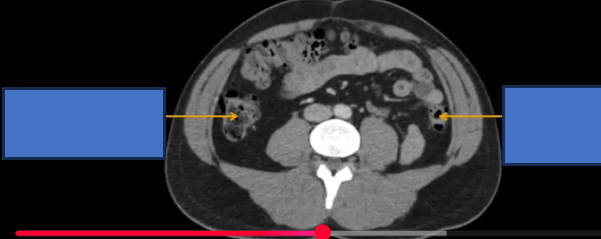

cơ chéo ngoài? trong? ngang b?

cq trong hình ?